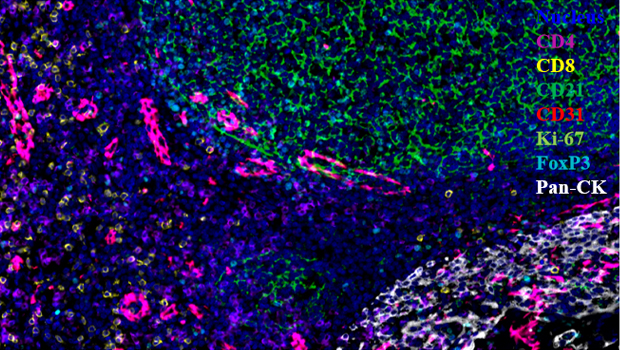

服务案例

Nucleus,CD4,CD8,CD21,CD31,Ki-67,FoxP3,Pan-CK